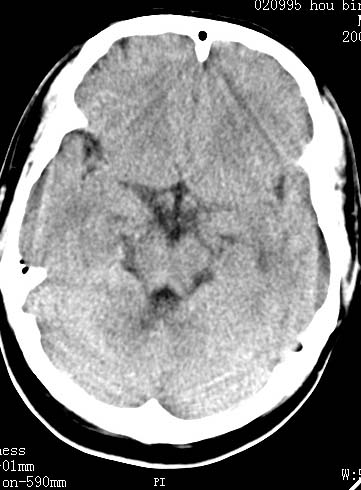

以下是引用clj20在2007-8-29 9:47:00的发言:[br]蛛网膜下腔出血,左侧额叶不均匀密度影,占位效应明显,界限不清。支持:占位性病变,建议增强!

以下是引用xulianj在2007-8-29 20:15:00的发言:[br]蛛网膜下腔出血,左侧额叶不均匀密度影,占位效应明显,界限不清。支持:占位性病变,建议增强!

以下是引用jiangjing在2007-8-29 14:33:00的发言:[br]左侧额叶不均匀密度影[低密度为主,边缘见等密度环环绕]占位效应明显,界限不清。支持:占位性病变,建议增强! [br][br]